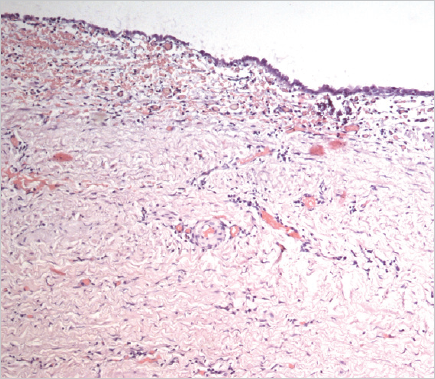

Histological examination of the removed paraurethral cyst was performed (Fig. 6–8).

Fig. 6.The wall of the paraurethral cyst, surgical material. Hematoxylin-eosin staining, ×100. The cyst wall is represented by fibrous tissue with moderate chronic inflammation, fresh hemorrhages (intraoperative) and covered with a transitional epithelium

Рис. 6.Стенка парауретральной кисты, операционный материал. Окраска гематоксилином и эозином, ×100. Стенка кисты представлена фиброзной тканью с умеренно выраженным хроническим воспалением, свежими кровоизлияниями (интраоперационными) и покрыта переходным эпителием

Fig. 7.The wall of the paraurethral cyst, surgical material. Hematoxylin-eosin staining, ×100. Epithelium with signs of dystrophia and minimal desquamation are represented

Рис. 7.Стенка парауретральной кисты, операционный материал. Окраска гематоксилином и эозином, ×100. Эпителий с признаками дистрофии и минимальной десквамации

Fig. 8.The wall of the paraurethral cyst, surgical material. Hematoxylin-eosin staining, ×100. Foci of epithelial lining atrophy are determined

Рис. 8.Стенка парауретральной кисты, операционный материал. Окраска гематоксилином и эозином, ×100. Определяются очаги атрофии эпителиальной выстилки